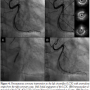

Coronary angiography was performed through the right radial artery. The angiogram revealed findings similar to the MDCT. First, the RCA could be cannulated with a 5 Fr Heartrail™ Ikari Left 4.0 curve (Terumo Corporation, Tokyo, Japan) (Figure 3A). After the 0.014˝ Asahi Sion™ guidewire (Asahi Intecc, Nagoya, Japan) was inserted into the RCA, the other 0.014˝ Runthrough™ NS guidewire (Terumo Corporation) was inserted into the anomalous origin of the LAD with pulling up and rotating counter-clockwise the guiding catheter a little.

The stenosis was evaluated by intravascular ultrasound (IVUS) ViewIT® (Terumo Corporation) (Figure 3B). The IVUS showed a focal eccentric plaque with attenuation in the LAD lesions. A 2.5 x 12 mm Xience V™ stent (Abbott Vascular, Santa Clara, California) was then implanted at 12 atm (Figures 3C and 3D). Then, the same guiding catheter could cannulate into the LCX that arose from the separate ostium in the posterior right coronary cusp (Figure 4A). The 0.014˝ Runthrough™ NS guidewire was inserted into the LCX, and IVUS showed a focal concentric fibrous plaque with negative remodeling in the LCX lesions (Figure 4B). A 2.75 x 15 mm Xience V stent was implanted at 12 atm (Figures 4C and 4D). The final angiogram showed optimal angiographic results in both lesions. The procedure time was 45 minutes, with 19.5 minutes of fluoroscopy and 125 ml of contrast used. The patient had no complications during hospitalization and was discharged the next morning.